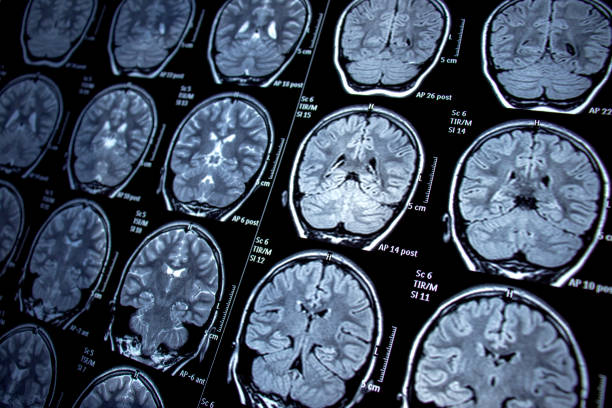

- 技術助力定位:隨著功能性磁共振成像(fMRI)等先進成像技術的發展,外科醫生能夠定位癲癇區域,并確定大腦相應區域手術可能導致的術后缺陷。

- 預后較好情況:MRI 上具有電臨床一致的結構性病變的患者預后最好,60% 至 70% 的病例癲癇發作能減少。

- 預后較差情況:患有顳葉外病灶、局灶性至雙側強直陣攣性癲癇、影像學正常、精神合并癥以及學習障礙的患者通常手術成功率較低。

研究表明骨髓抽吸和隨后的細胞制備后,通過選擇性大腦后動脈導管插入術將BMMC注入。對患者進行6個月的隨訪。手術安全性、癲癇發作頻率、神經心理學評估、EEG變量、常規腦磁共振成像和海馬體積測定被視為結果測量指標。報告了與手術相關的任何嚴重并發臨床事件或不良反應。未觀察到其他病變,也未觀察到顯著的海馬體積變化。

EEG記錄顯示θ活動和尖峰密度降低。6個月后,8名患者 (40%) 不再癲癇發作。隨時間推移,記憶評分顯著增加。BMMC自體移植用于治療顳葉癲癇是可行且安全的。這項新研究中實現的癲癇控制支持干細胞移植對MTLE-HS患者的治療潛力。